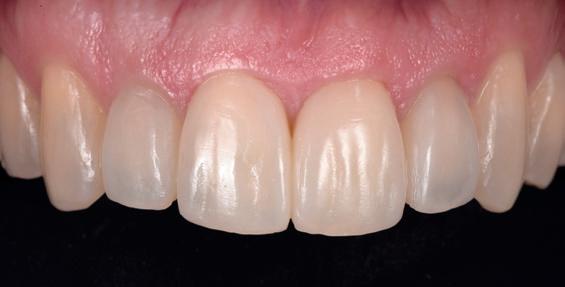

Case 1: Anterior tooth restoration with composite

Restorations with BEAUTIFIL II LS, BEAUTIFIL Flow Plus X and OneGloss by Erik-Jan Muts, M.Sc., Netherlands